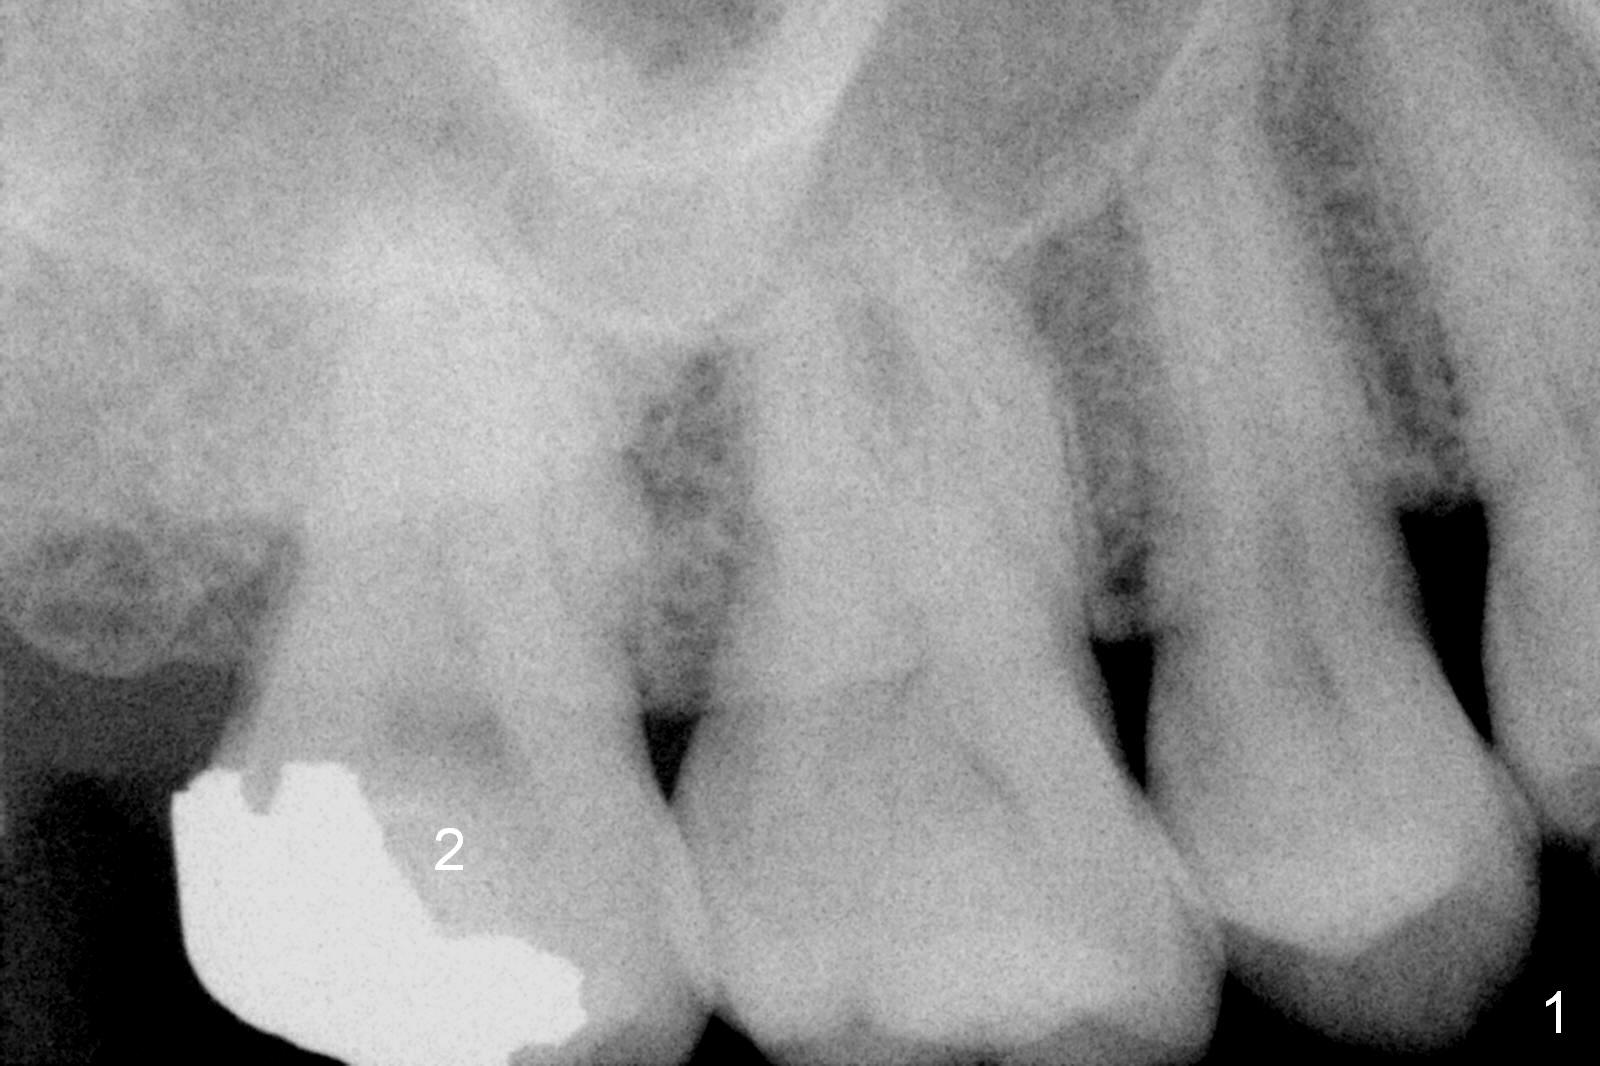

A 52-year-old man has had mild cold sensitivity for the last 3 years since RCT was done at the tooth #2 (3 canals, MB2 not found, Fig.1 (preop), 2 (taken today, pain more severe)). After discussion of treatment options (including RCT retreat), the patient chooses extraction and implant. The planned implant is 6.5x9 mm (Fig.3). As expected, the 3 roots are fused (Fig.4). The socket is single and triangular (Fig.6 green outline (black one: gingival margin)). What is not really expected is the presence of the possible MB2 canal (Fig.5 *). The mesiodistal width of the buccal roots and palatal one are 6.5 and 4.5 mm, respectively. The diameter of the planned immediate implant is estimated to be 5 mm. The socket depth is 11 and 13 mm to the crest and the gingiva, respectively. After use of Magic Expanders (ME) from 3.0-4.3 mm for sinus lift, a 5x11 mm dummy implant is placed. The implant (Fig.7 red circle) has 3 pointed contact so it is stable, but it is placed apically (Fig.8). After removal of the dummy implant, allograft is placed (.5-1.5 mm) before insertion of a 5.5x11 mm implant with satisfactory stability (Fig.9). Postop, the patient reports light bloody nasal discharge with bone graft. Ideally with the narrow mesiodistal socket, it is unnecessary to penetrate the sinus floor with ME. A 5x9 mm dummy implant should have been placed with well-controlled implant placement depth. It is followed by inserting an implant .5 mm larger for the maxilla. IBS implants are easy to achieve primary stability. Insertion torque of 20 Ncm is sufficient to load abutment (5x4(4) mm) and immediate nonfunctional provisional.